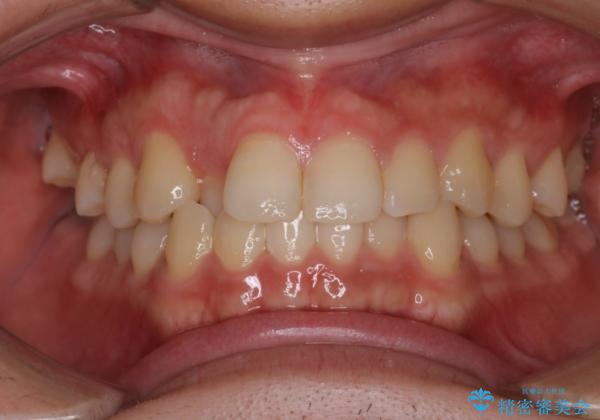

- 前歯のがたつきを主訴に来院されました。初診時、右上2番の口蓋側転位と右下7番の舌側傾斜が認められました。

インビザラインにてIPRと歯列弓拡大を行い、ゴム掛けで噛み合わせを改善する治療計画を立てました。

マウスピースの使用時間が短いため、シュミレーション通り進むか不安でしたが

治療期間1年で、主訴である前歯のがたつきを改善出来、

奥歯の噛み合わせも良くなりました。